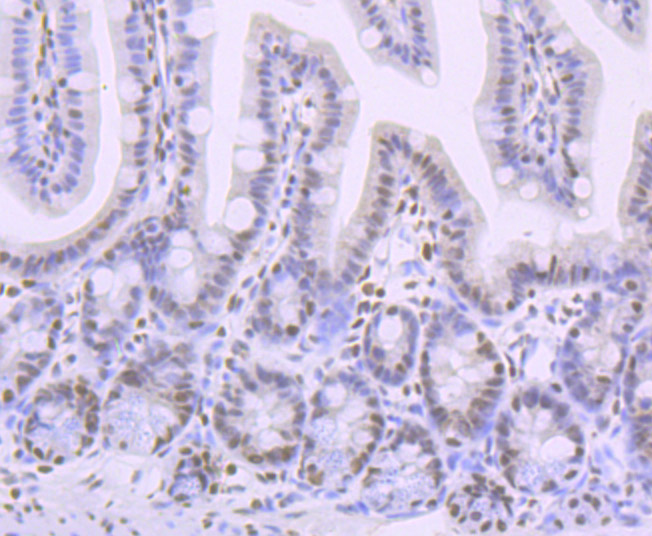

Immunohistochemical analysis of paraffin-embedded mouse colon tissue using anti-Phospho-Creb (S133) antibody. Counter stained with hematoxylin.